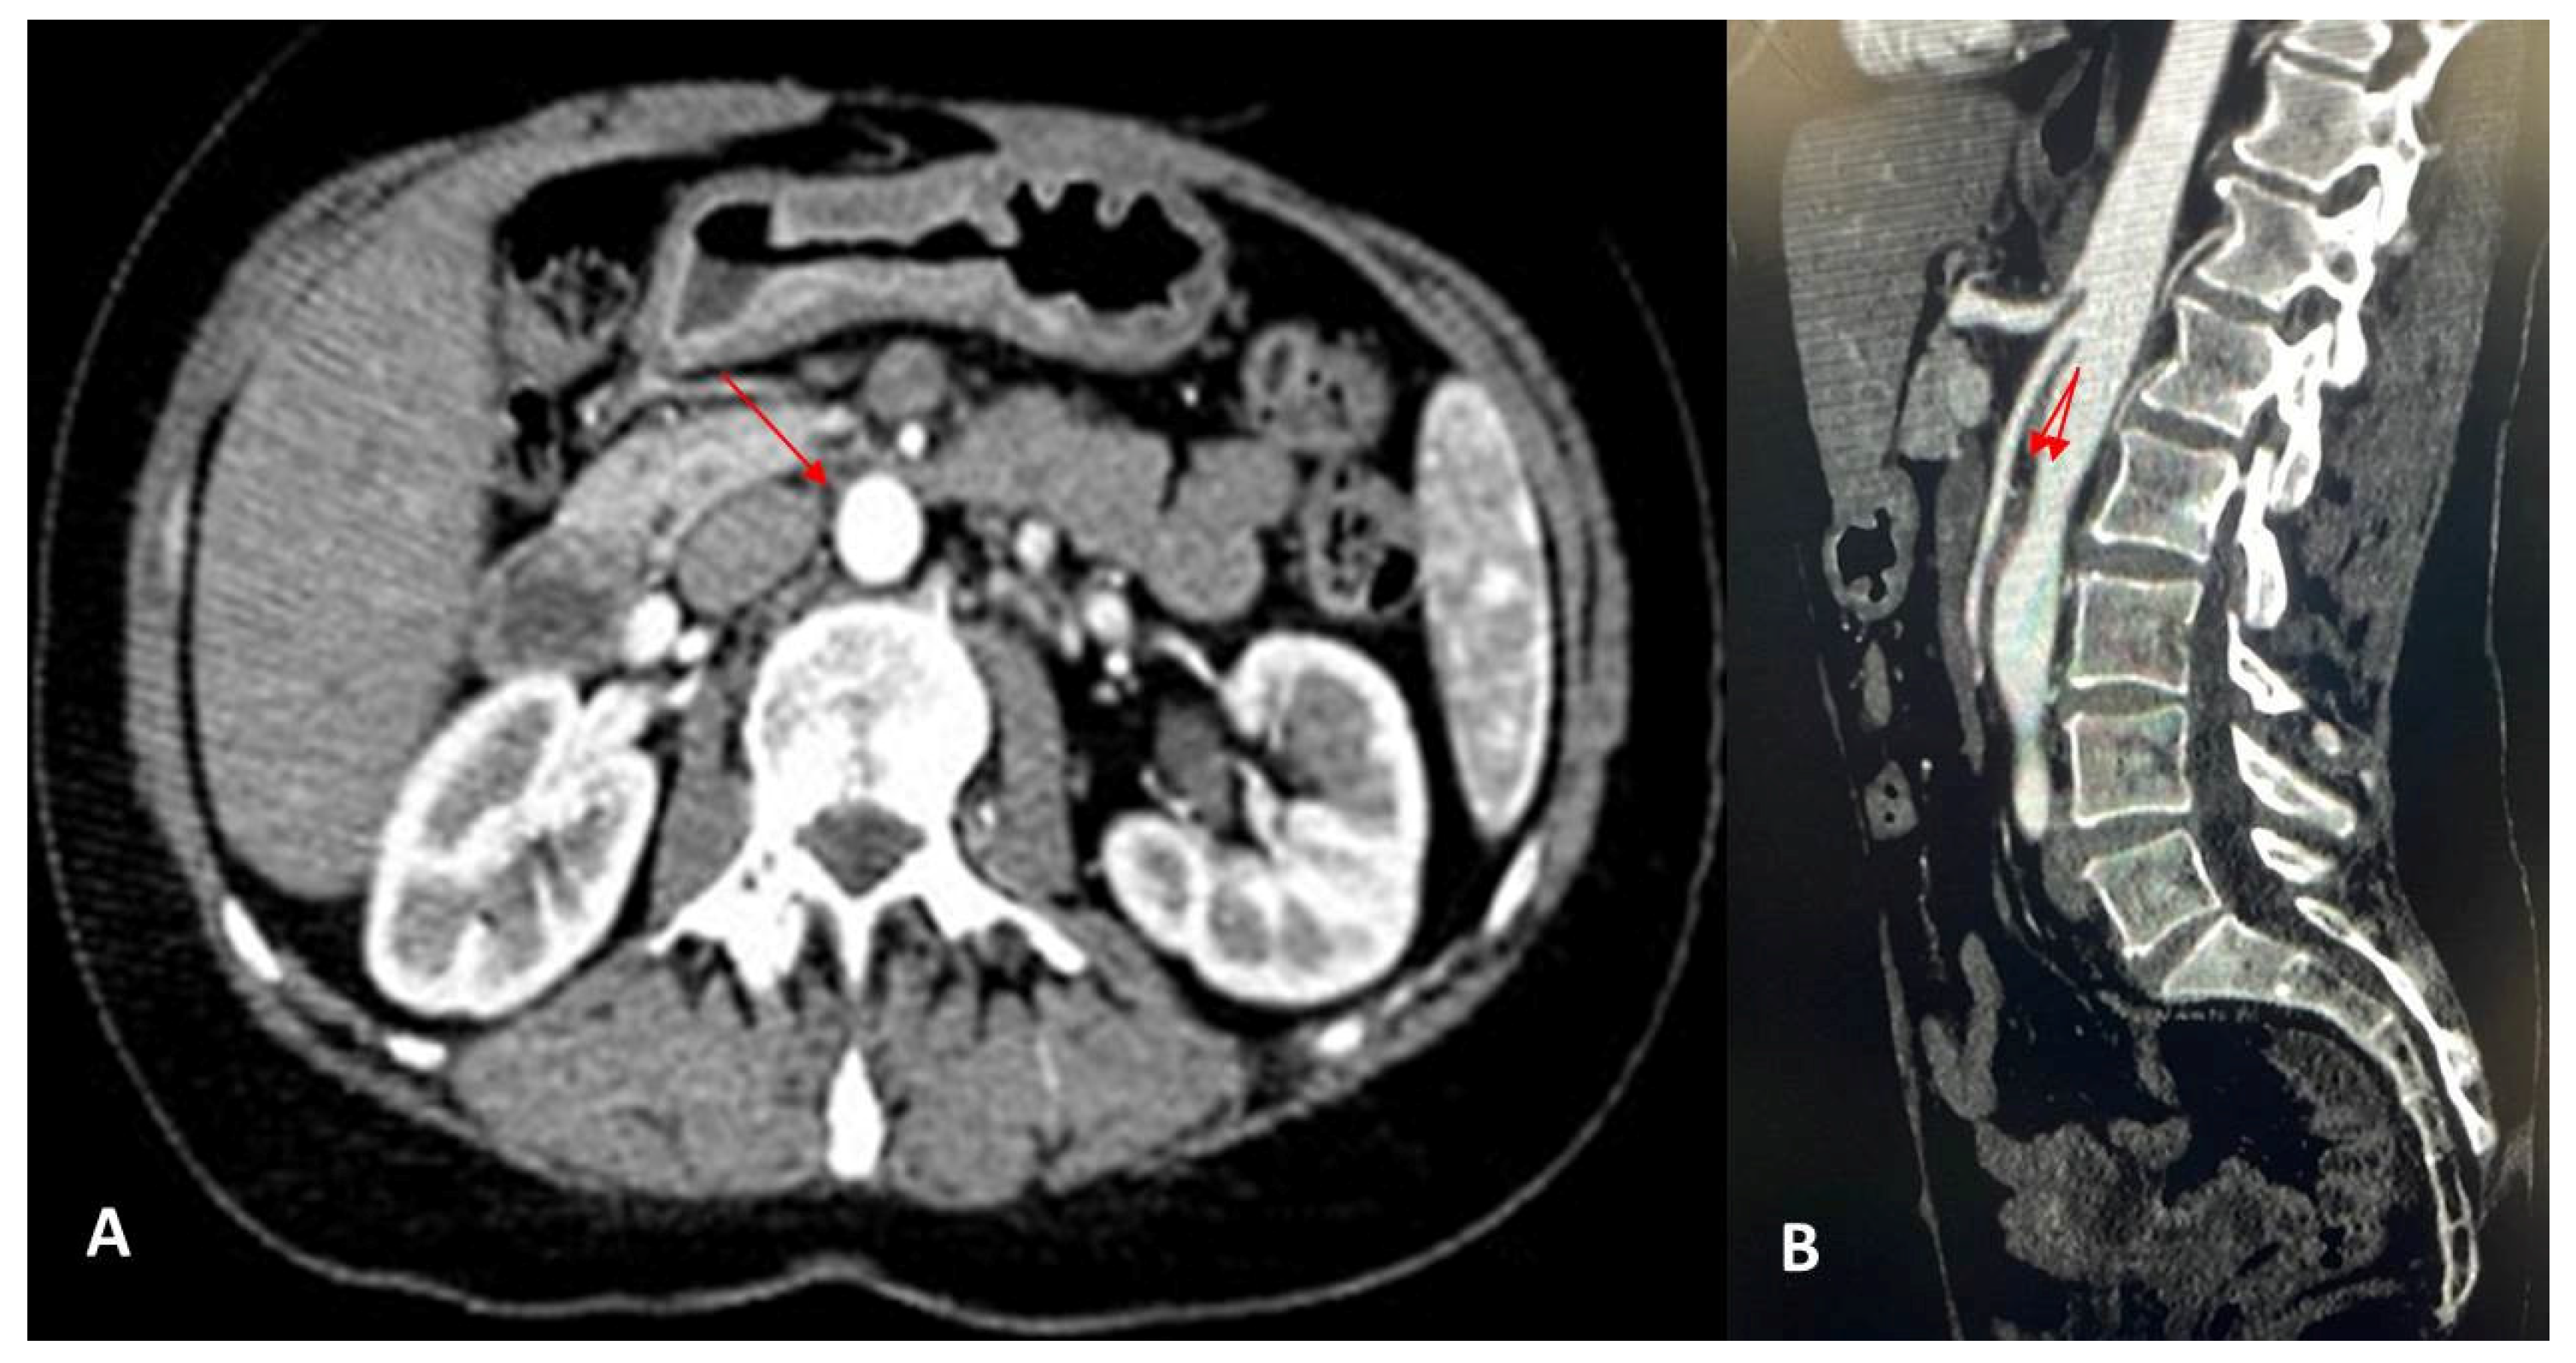

| Farina et al., 2020 [22] | 27-year-old male | Painful post-prandial crises at the sub-acute onset, located at the epigastrium | Doppler US CT |

Endovascular stent grafting |